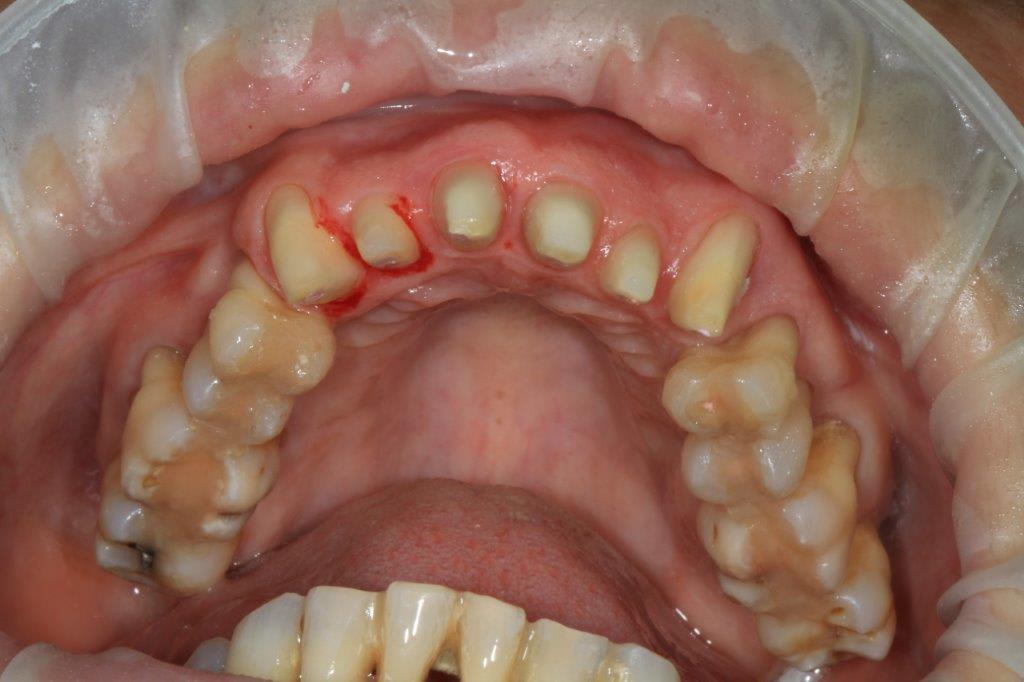

retour de vacances et reprise ... Un mois sans voir la patiente, ça permet de contrôler l'hygiène et la motivation.

Toujours un petit suintement purulent sur 33 et 16, mais globalement rien à voir avec le début.

Les provisoires sur les antérieures maxillaire n'ont pas bougées, ce qui est rassurant.

J'ai retouché les contacts 14/44/43 et 24/34/33 car il y a toujours une légère surcharge

photos avec le portable, pas terrible.